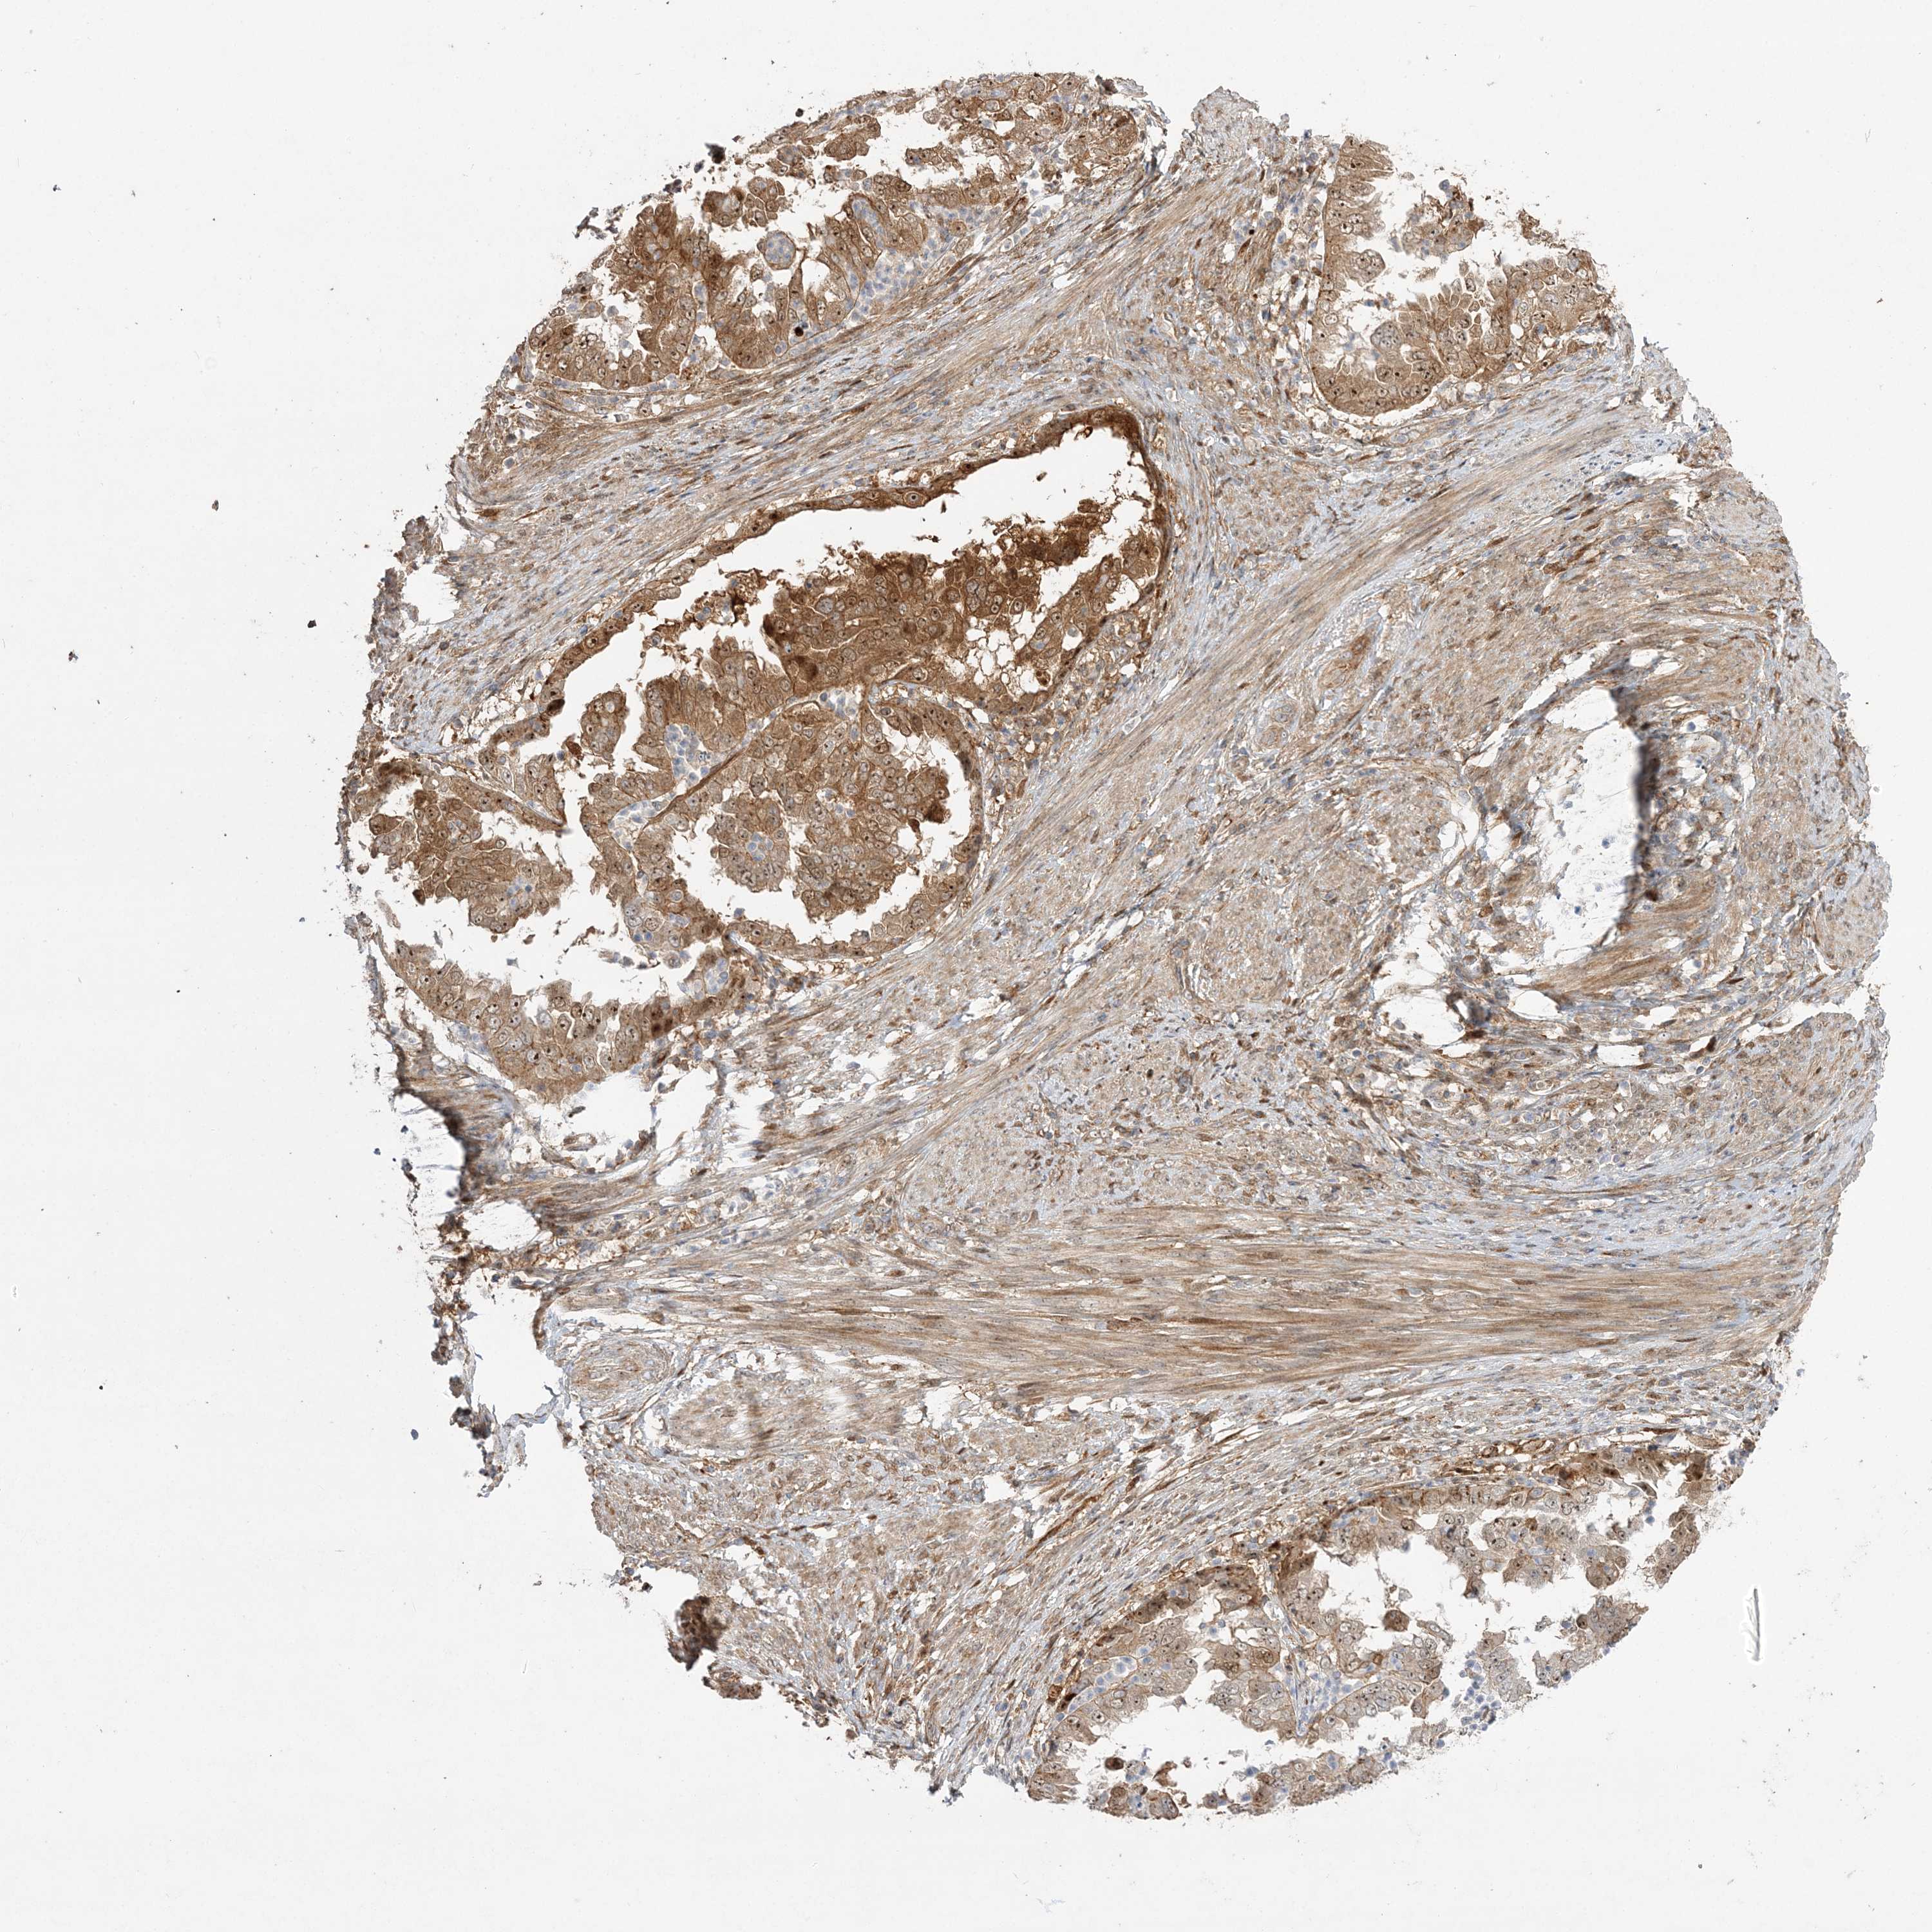

ENDOMETRIAL CANCER - Protein expressioni

A mouse-over function shows sample information and annotation data. Click on an image to view it in a full screen mode. Samples can be filtered based on level of antibody staining by selecting one or several of the following categories: high, medium, low and not detected. The assay and annotation is described here.

Note that samples used for immunohistochemistry by the Human Protein Atlas do not correspond to samples in the TCGA dataset.

Antibody stainingi

Antibody staining in the annotated cell types in the current human tissue is reported as not detected, low, medium, or high, based on conventional immunohistochemistry profiling in selected tissues. This score is based on the combination of the staining intensity and fraction of stained cells.

Each image is clickable and will lead to virtual microscopy that enables deeper exploration of all samples and also displays staining intensity scores, fraction scores and subcellular localization as well as patient and tissue information for each sample.

Antibody HPA036295

Antibody HPA036296

Staining

High

Medium

Low

Not detected

Intensity

Strong

Moderate

Weak

Negative

Quantity

>75%

75%-25%

<25%

None

Location

Nuclear

Cytoplasmic/membranous

Cytoplasmic/membranous,nuclear

Adenocarcinoma, NOS